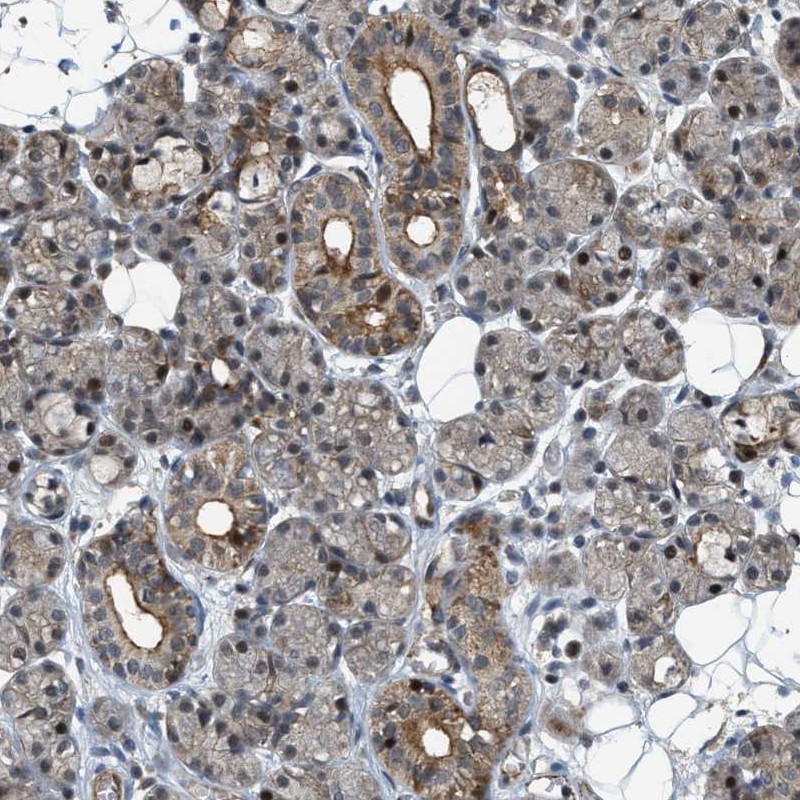

Immunohistochemical staining of human salivary gland shows weak cytoplasmic and nuclear positivity in glandular cells.